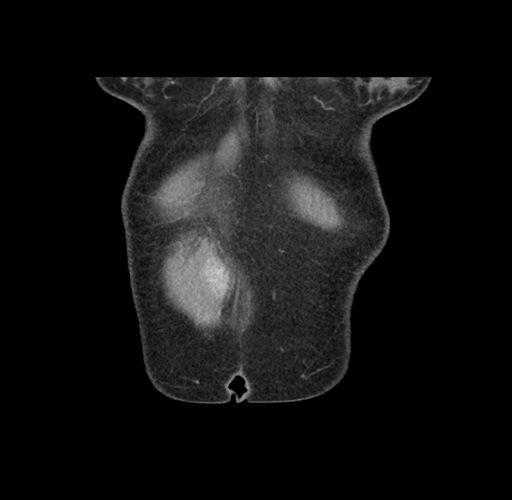

Imaging Analysis

Look through the patient's CT scan to identify any areas of concern for the necessary procedure.

Based on your CT findings, which issue(s) would give reason for "planned slowing down moment(s)" in this case?

Considering a standard left lateral sectionectomy procedure, what step(s) of the operation would you do differently in this case ?